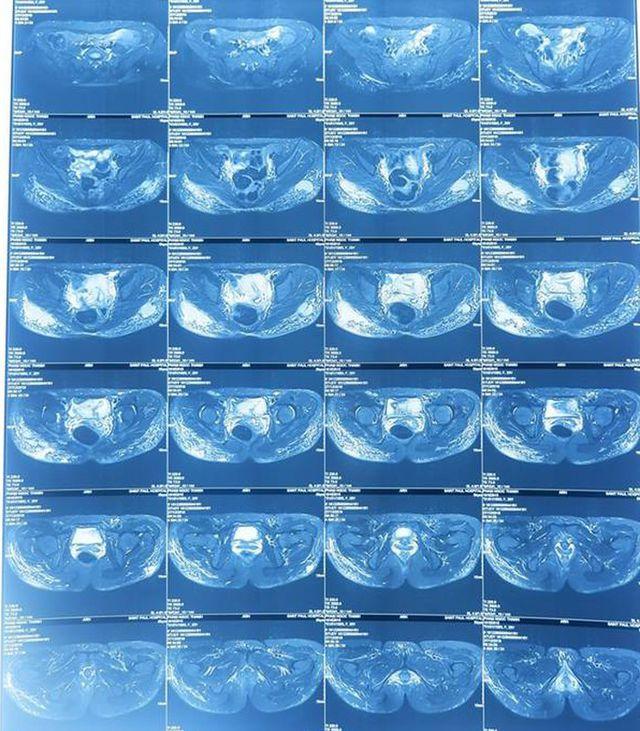

Tại BV E cũng từng tiếp nhận bệnh nhân nhiễm trùng, sưng, tấy đỏ ở mông. Qua kết quả khám, chụp cộng hưởng từ, các bác sĩ thấy 2 khối dịch lớn có tính chất trong suốt, kèm theo rất nhiều hạt nhỏ rải rác khắp 2 bên mông bệnh nhân.

Hình ảnh điển hình dựng lại trên cộng hưởng từ là hình ảnh các hạt silicon trắng xóa như mưa sao băng do silicon lỏng gây ra. Các bác sĩ rất khó để lấy silicon đã bơm vào vòng ba cho bệnh nhân.